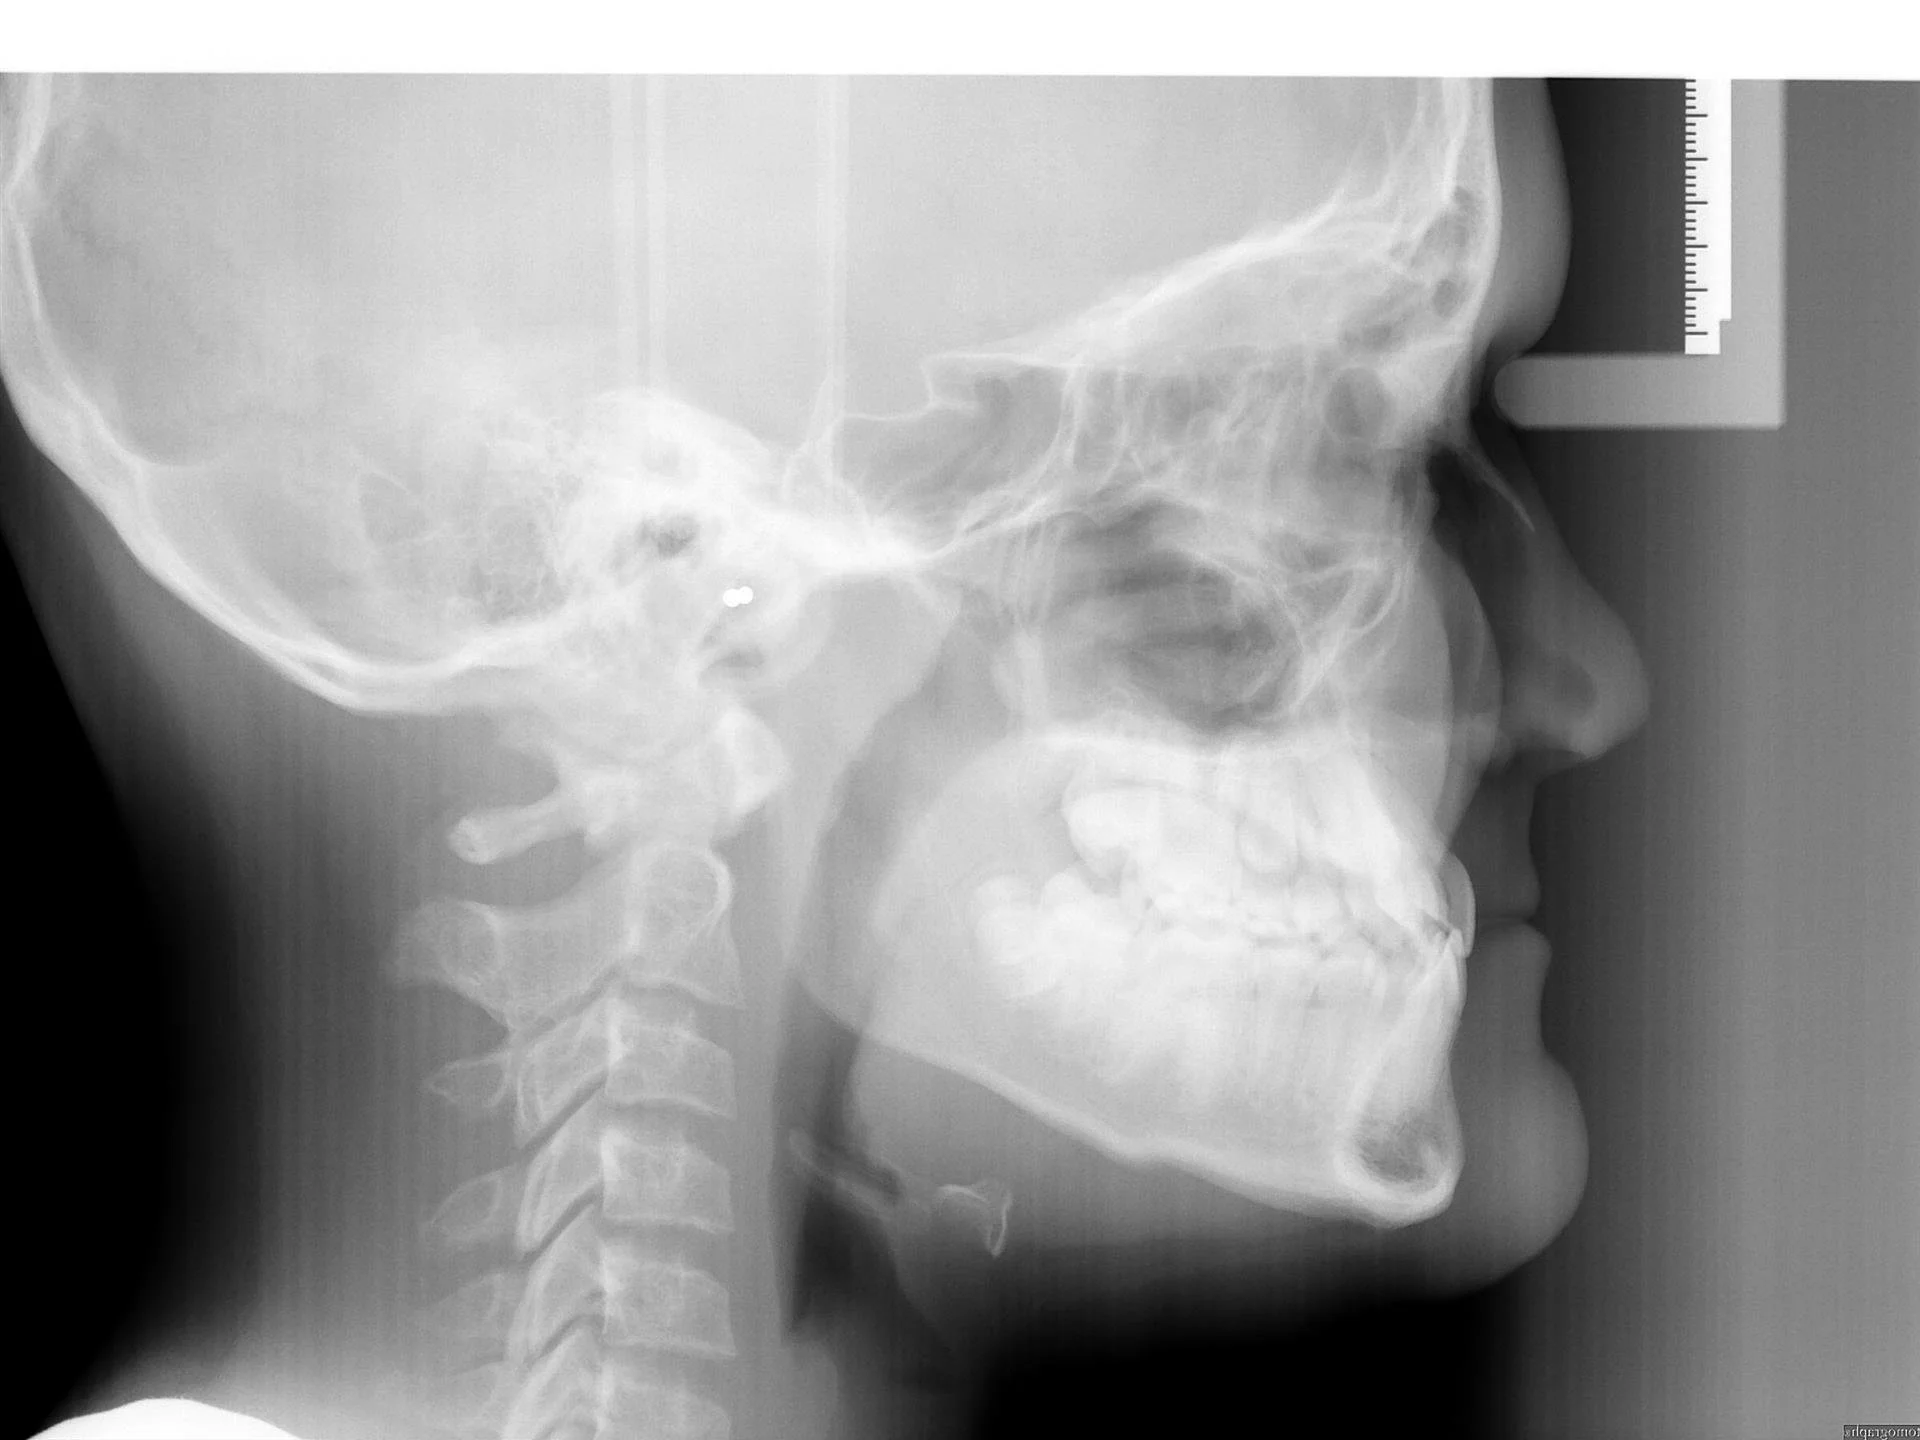

Subject with Class III jaw growth

Same subject 4 years later: Upper incisors are proclined, and lower incisors occlude in front of the upper incisors.